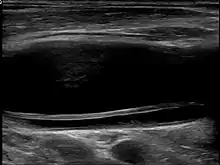

Carotid artery dissection

Carotid artery dissection is a separation of the layers of the artery wall supplying oxygen-bearing blood to the head and brain and is the most common cause of stroke in young adults.[1] (Dissection is a blister-like de-lamination between the outer and inner walls of a blood vessel, generally originating with a partial leak in the inner lining.)[2]